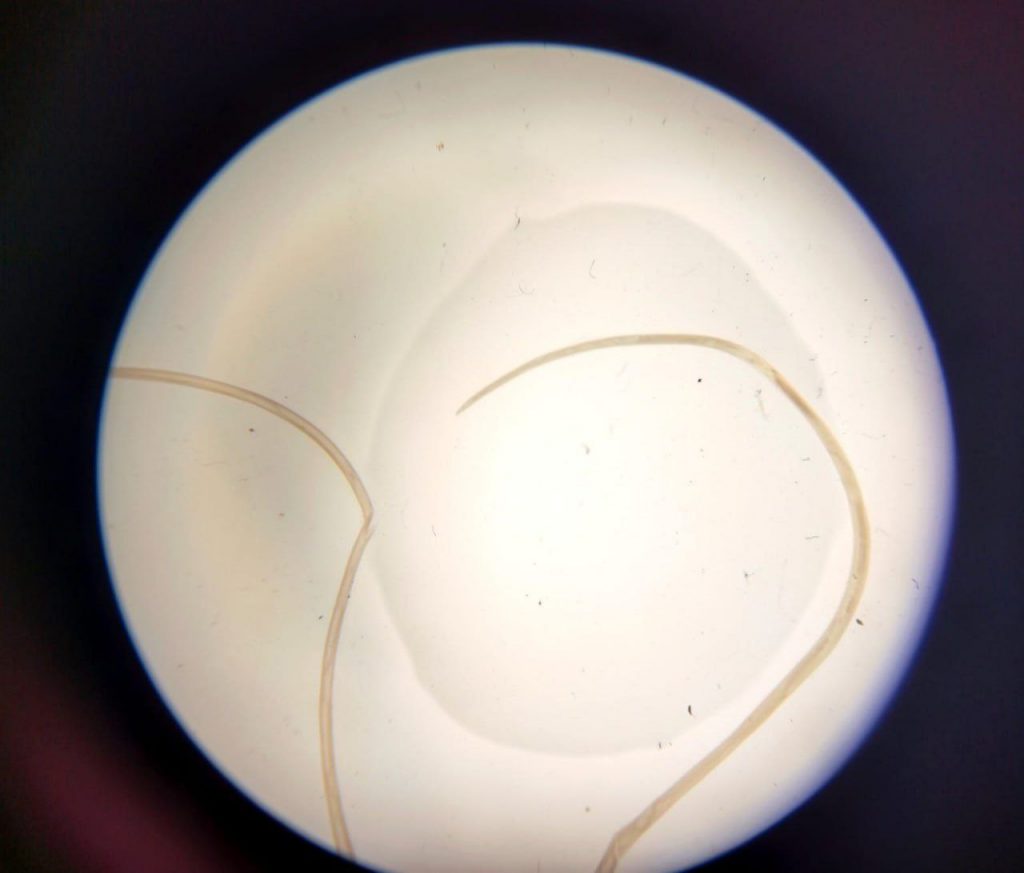

Однак частіше паразит уражає ділянки спини, плеча та передпліччя. Видаляють паразита оперативно, і вилучають, як правило, одного живого гельмінта довжиною 10-15 см.